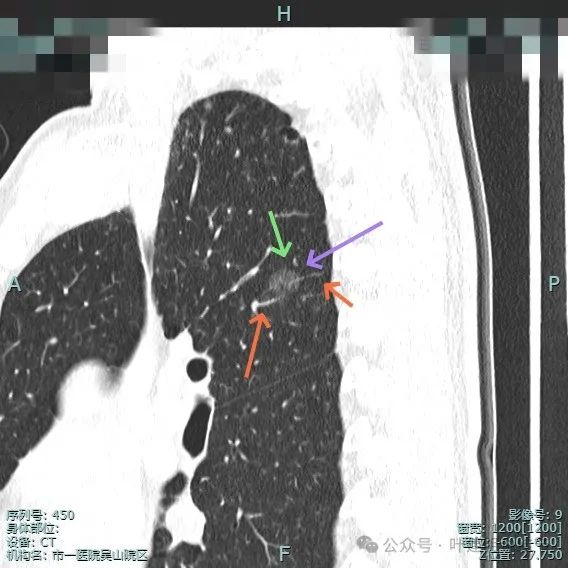

再来看主病灶右上叶后段病灶6的靶重建影像:

图片

病灶磨玻璃密度,未见明显实性成分,但有血管进入。

血管穿行明显,表面有毛刺征,灶内有空泡征。

分叶明显,灶内点状高密度(血管穿行)表面有细小毛刺征。

灶内密度略显不均,有空泡征,表面有毛刺征。

毛刺与血管进入,整体是纯磨,轮廓与边界清。

少许毛刺,整体轮廓清。

血管穿行并发现细小分支的样子,表面不平有细毛刺,灶内有小空泡征。

血管穿行并略有增粗,表面不平有浅分叶,整体轮廓与边界清。

血管进入并有发出分支,边缘有细毛刺,表面不光滑,整体轮廓清,瘤肺边界清楚。